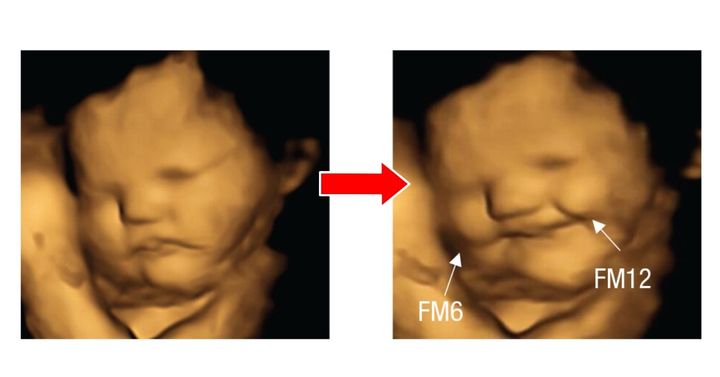

具体的には、ニンジン味にさらされた胎児は「笑い顔」の反応が多く、ケール味にさらされた胎児は「泣き顔」の反応が多く見られました。

ニンジン味にさらされた後、胎児は「笑顔」になった/ Credit: Beyza Ustun et al., Psychological Science(2022)

やはり胎児は全体的に、ニンジン味のような野菜の中でも甘味の強いものに好意的な反応を示し、ケール味のような苦味の強いものには嫌悪感を抱く傾向があるようです。